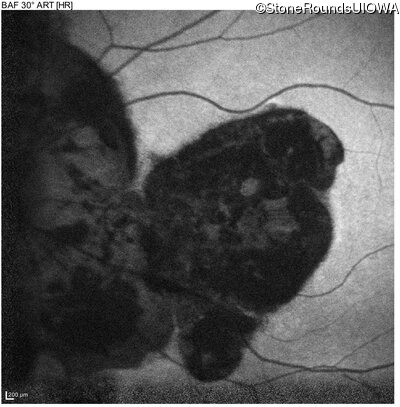

Blue Autofluorescence - Left - 10/140

Exemplar